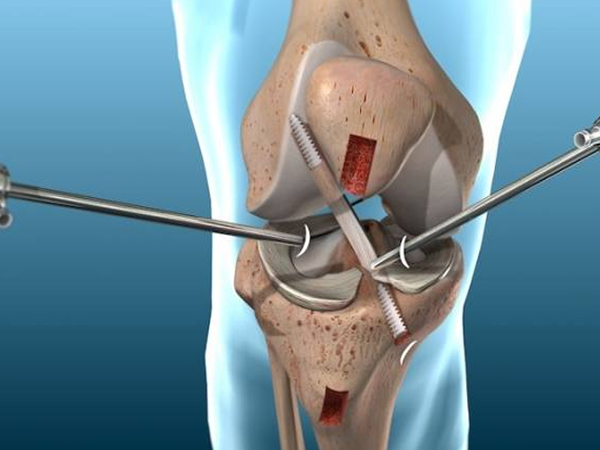

He has completed MBBS, MS [ORTHOPAEDICS], DNB [ORTHOPAEDICS], FIJR, FIAS, FIAT followed by specialized fellowships in Advanced Trauma, Robotic & Conventional Joint Replacement, and Arthroscopy. His clinical expertise spans adult and pediatric trauma, fracture management, joint replacement surgeries, sports injuries, and spine-related conditions.

Dr. Anmol has treated 2000+ patients and has been involved in 500+ orthopaedic surgeries, including complex trauma cases and advanced joint replacement procedures. His exposure to robotic joint replacement and arthroscopy allows him to offer precise, minimally invasive solutions with faster recovery and improved outcomes.